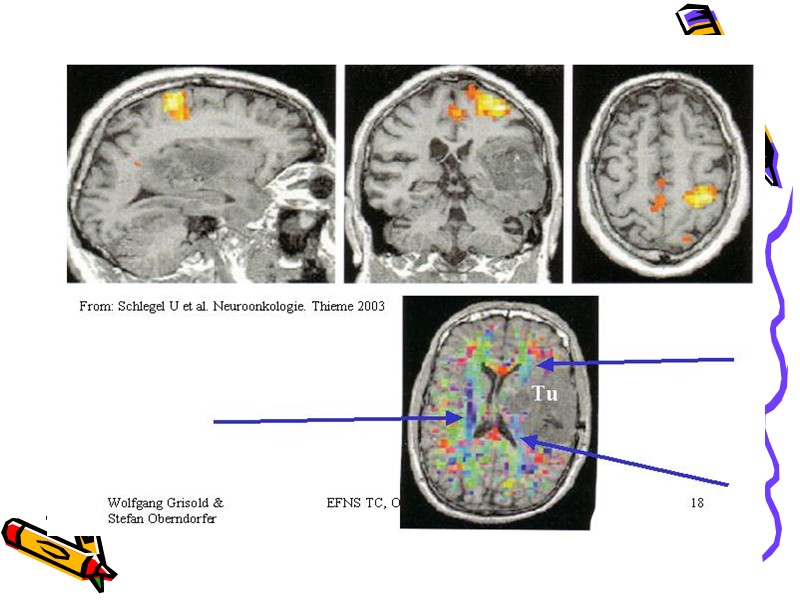

патофизиология эпилепсии наличие группы нейронов с патологической активностью (эпи-очаг) способность навязывать, распространять активность слабость системы протиэпилептической защиты

Intensive Video-EEG-Monitoring

Рекомендации, базирующиеся на принципах доказательной медицины (диагностика) 1. диагноз выставляет невролог или эпилептолог. 2. необходимо провести диф.диагностику между эпилепсией и эпи-синдромом. 3.следует определить тип приступа. 4. отсутствие изменений на ЭЭГ не отрицает диагноз эпилепсии 5. МРТ- наиболее информативный метод нейровизуализации.